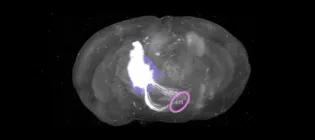

Using spatial transcriptomics we show the distance from a brain bleed (A) is associated with both protective (B) and harmful (C) immune responses.

Inflammation shapes recovery after brain injury. I investigate how to promote helpful immune responses to brain bleeding and limit harmful ones.

James.Loan@ed.ac.uk